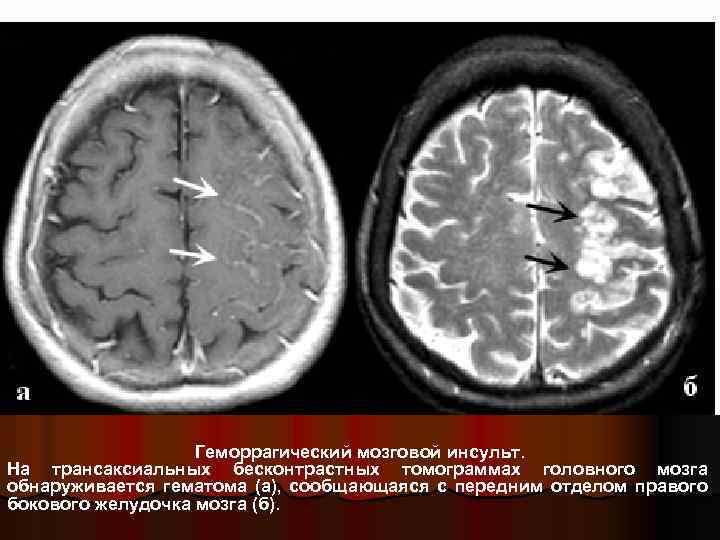

Геморрагический мозговой инсульт. На трансаксиальных бесконтрастных томограммах головного мозга обнаруживается гематома (а), сообщающаяся с передним отделом правого бокового желудочка мозга (б).